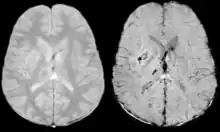

Comparison of diffuse axonal injury imaged with conventional GRE (left) and SWI (right) at 1.5 T

Comparison of hemorrhage imaged with conventional GRE (left) and SWI (right) at 1.5 T

The detection of micro-hemorrhages, shearing, and diffuse axonal injury (DAI) in trauma patients is often difficult as the injuries tend to be relatively small in size and can be easily missed by low resolution scans. SWI is usually run at relatively high resolution (1 mm3) and is extremely sensitive to bleeding in the gray matter/white matter boundaries making it is possible to see very small lesions increasing the ability to detect more subtle injuries.

Stroke and hemorrhage

Diffusion weighted imaging offers a powerful means to detect acute stroke. Although it is well known that gradient echo imaging can detect hemorrhage, it is best detected with SWI. In the example shown here, the gradient echo image shows the region of likely cytotoxic edema whereas the SW image shows the likely localization of the stroke and the vascular territory affected (data acquired at 1.5 T).

The bright region in the gradient echo weighted image shows the area affected in this acute stroke example. The arrows in the SWI image may show the tissue at risk that has been affected by the stroke (A, B, C) and the location of the stroke itself (D). The reason that we are able to see the affected vascular territory could be because there is a reduced level of oxygen saturation in this tissue, suggesting that the flow to this region of the brain could be reduced post stroke. Another possible explanation is that there is an increase in local venous blood volume. In either case, this image suggests that the tissue associated with this vascular territory could be tissue at risk. Future stroke research will involve comparisons of perfusion weighted imaging and SWI to learn more about local flow and oxygen saturation.